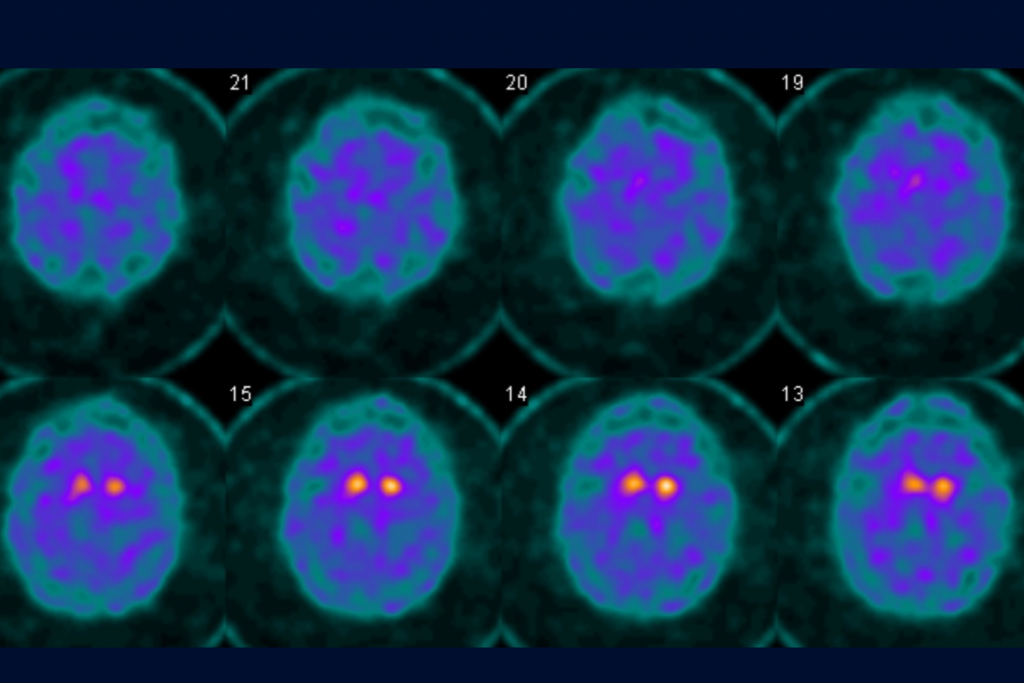

Bill is only in his fifties, but was diagnosed recently with Parkinson’s disease at UConn Health’s Brain and Spine Institute. The diagnosis was further supported through a DaTscan (dopamine transporter scan) using a radioactive tracer to confirm the disease’s hallmark – low dopamine in the brain.